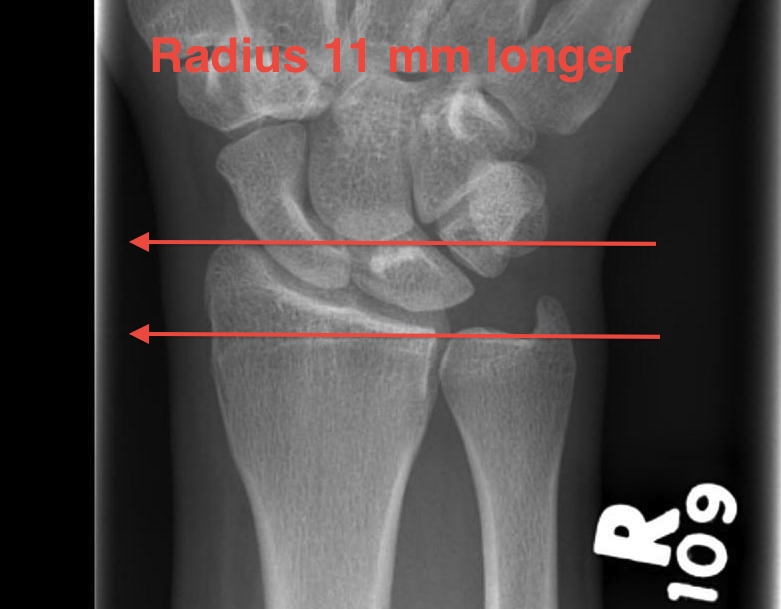

Radiological evaluation of the distal radius. If radial inclination What Is Volar Tilt Learn about the pathophysiology, classification, risk factors, clinical features, investigations and management of this injury. A line perpendicular to the long axis of the radius is drawn, and a. A smith's fracture is a type of distal radius fracture with volar angulation of the distal fragment, caused by falling backwards and planting the outstretched hand behind the body. The volar. What Is Volar Tilt.